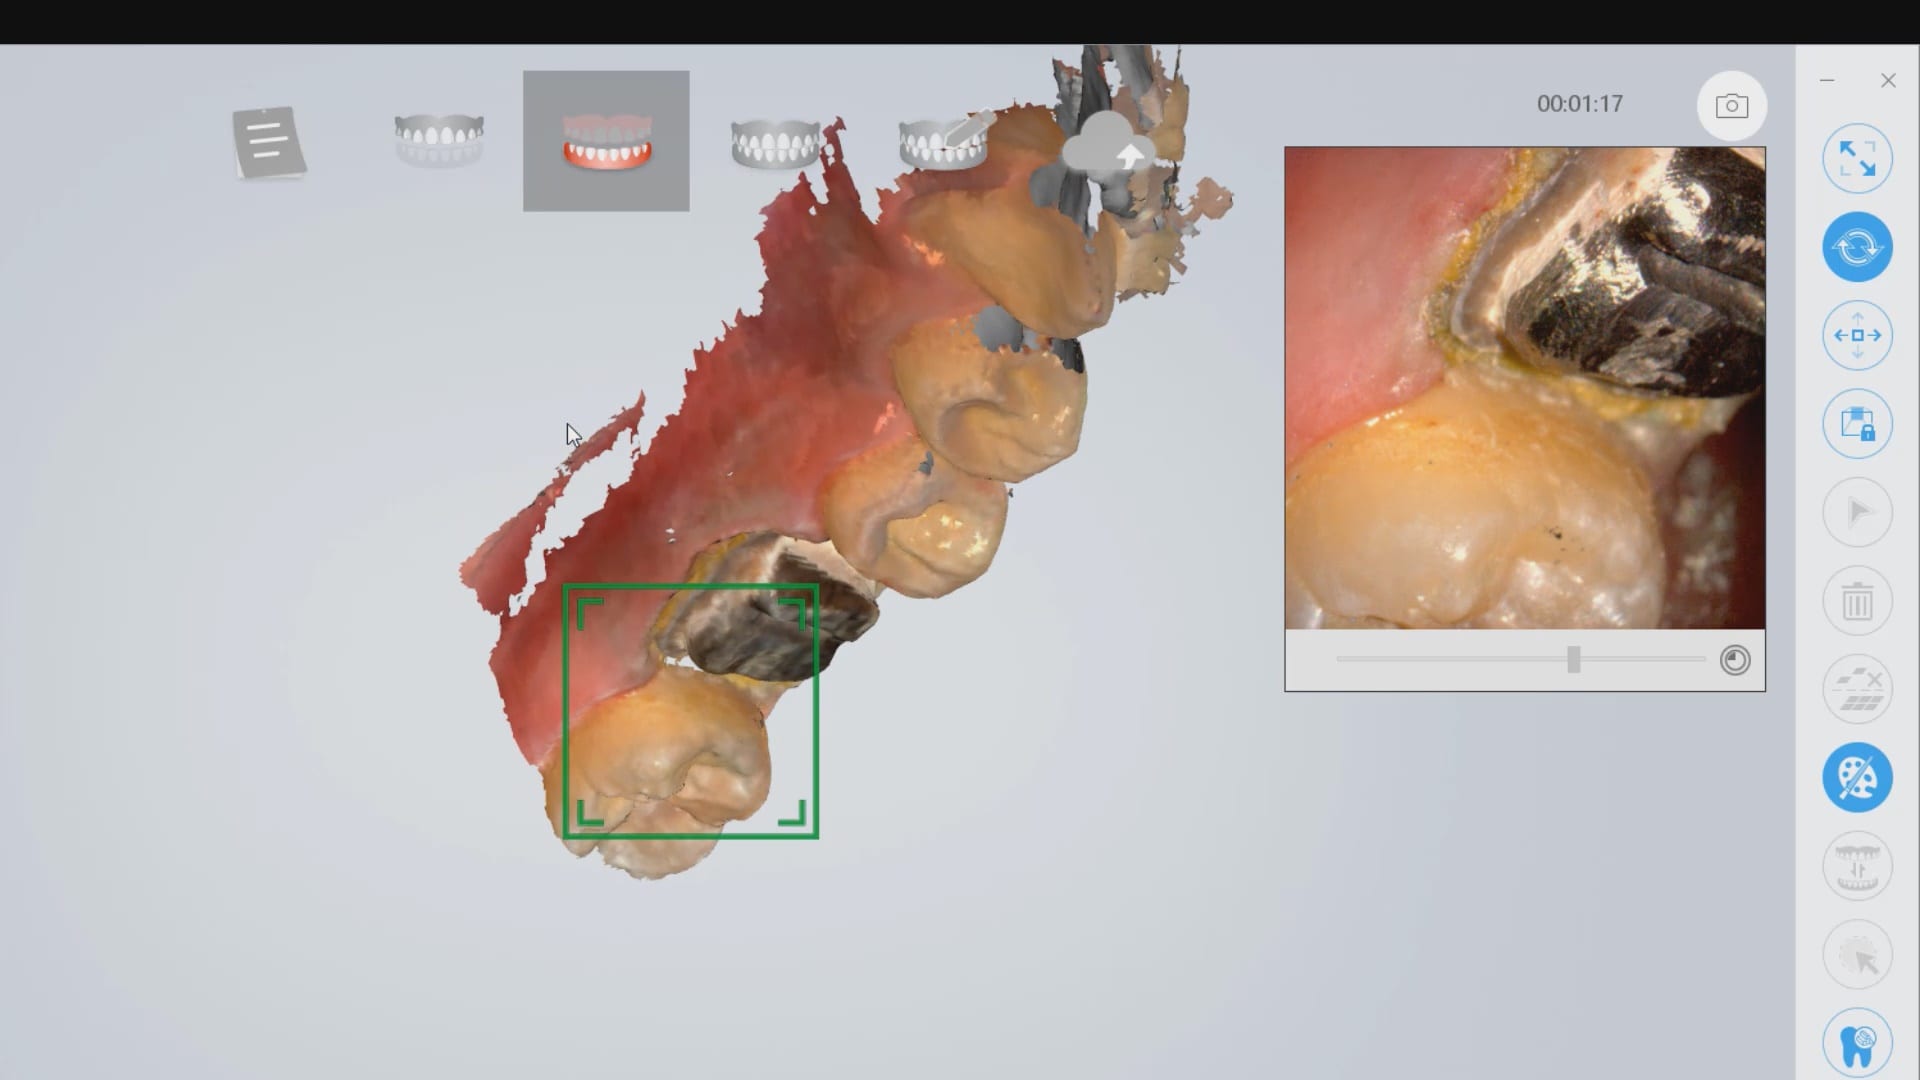

Lower First Molar Deep Margins Scanned by Shining AoralScan

In this video we demonstrate how the Aoralscan from Shinning 3D captures deep margins.

An old PFM crown warranted replacement due to open margins and recurrent decay. After the crown was removed, the margins were refined and the tissue was displaced with expasyl and retraction cord.

This video is deliberately captured slowly so a new user can appreciate how to hold the camera to capture the margins and the contacts of the adjacent teeth. You also have the opportunity to place your own margins and the path of draw before submit the case to the lab.